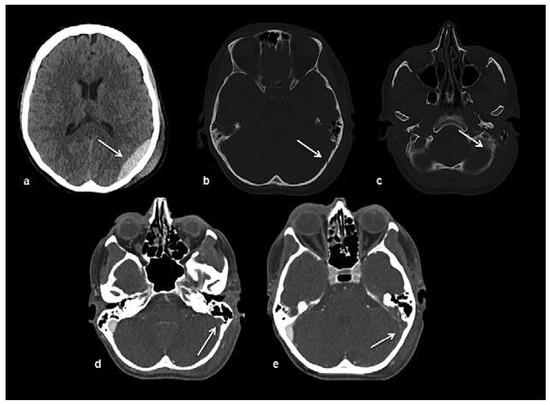

Head and brain trauma: general aspects and neuroimaging

by Johanna Maria Lieb, Christoph Stippich and Meritxell Garcia

In this article the general clinical aspects, imaging indications and different injury mechanisms of traumatic brain injury (TBI) are reviewed. In addition, the different imaging modalities and strategies are presented, including more specific imaging features of the various injuries. Computed tomography (CT) is [...] Read more.

In this article the general clinical aspects, imaging indications and different injury mechanisms of traumatic brain injury (TBI) are reviewed. In addition, the different imaging modalities and strategies are presented, including more specific imaging features of the various injuries. Computed tomography (CT) is the imaging modality of choice in the acute phase owing to its wide availability and short scanning time, as well as to its high sensitivity for the detection of fractures and acute bleeding. Although magnetic resonance imaging (MRI) is superior to CT in many other aspects, it plays no role in the acute phase. MRI, however, has been proven to be useful and complementary to CT in the subacute and chronic stages as well as in the case of inconclusive results on initial CT. Especially the use of standard sequences like fluid attenuated inversion recovery (FLAIR), diffusion and susceptibility weighted imaging (DWI and SWI) have been shown to increase the diagnostic potency in diffuse axonal injury, in mild brain trauma and also in more chronic stages of TBI. The use of more advanced MRI techniques such as diffusion tensor imaging (DTI), magnetic resonance spectroscopy (MRS), functional MRI (fMRI) and magnetic transfer imaging (MTI) can further complete the diagnostic evaluation and give insights into different pathophysiological processes in TBI. Full article